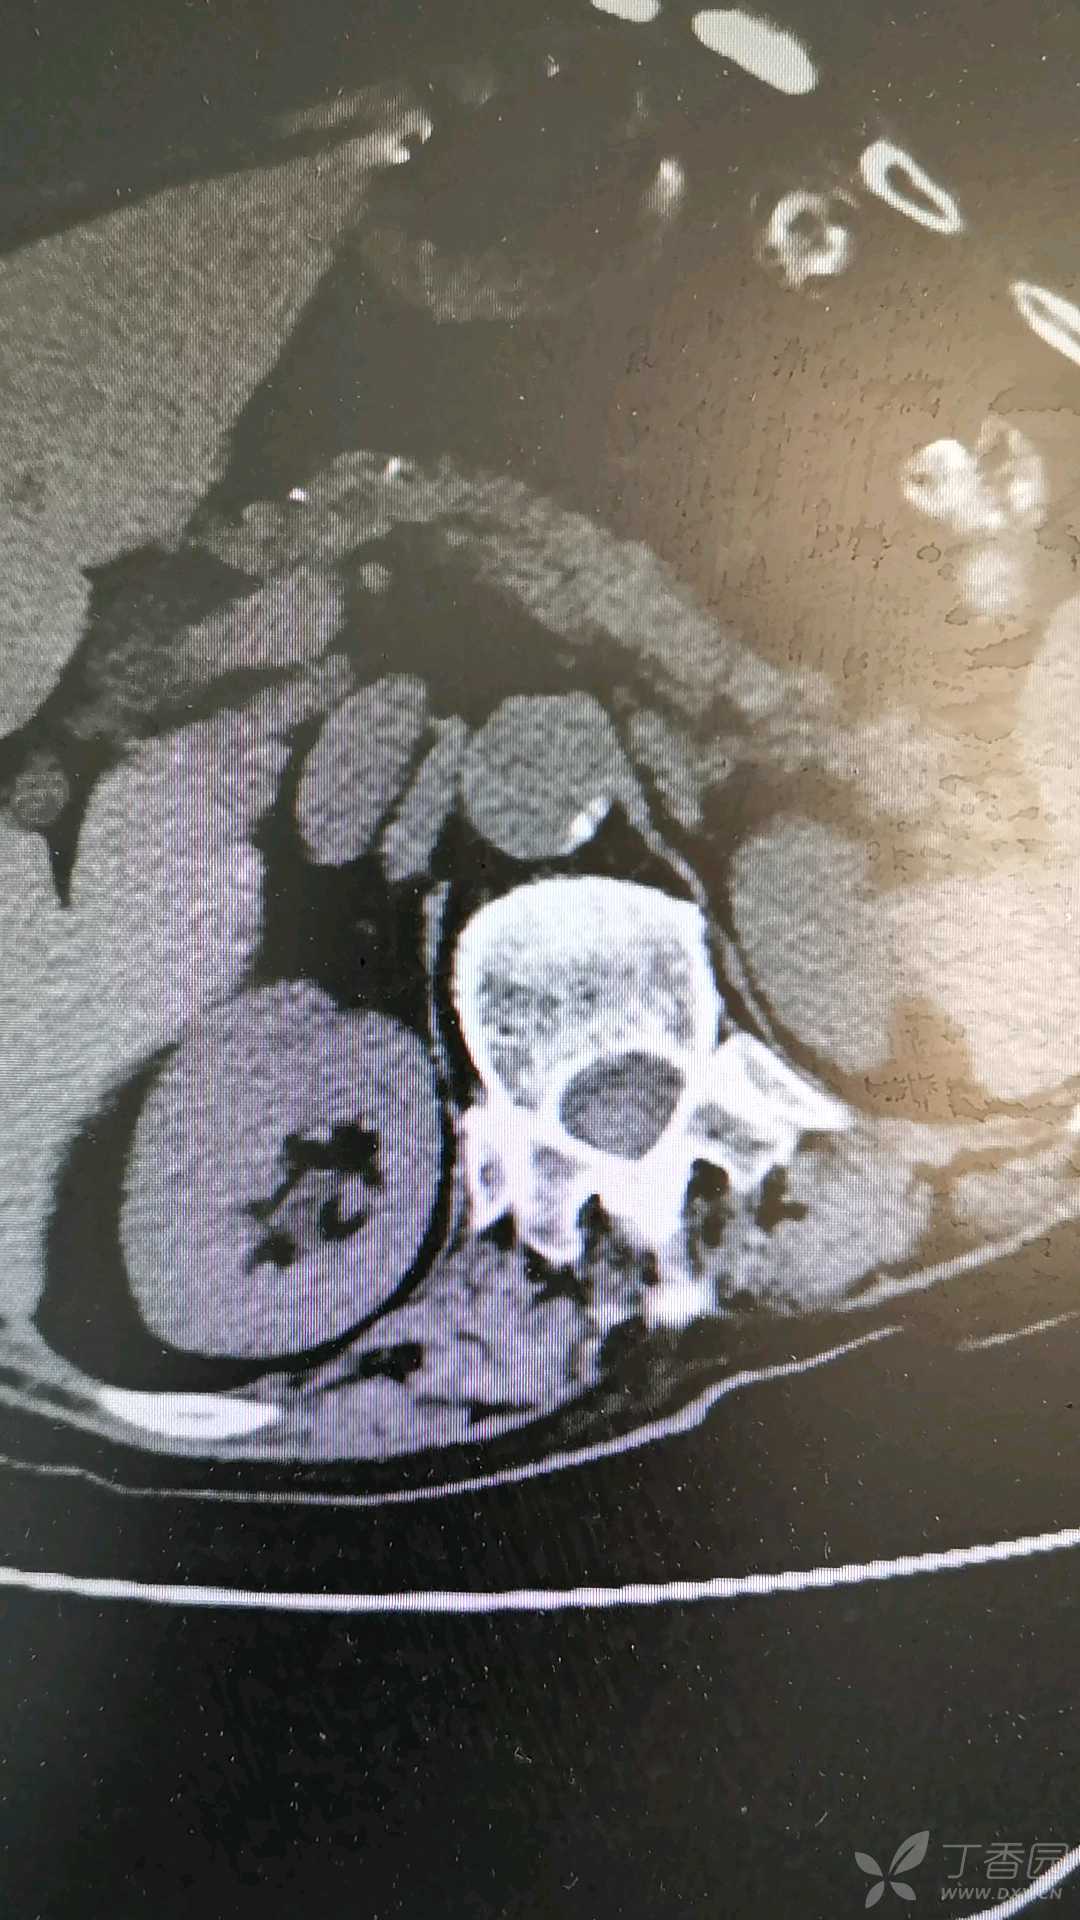

45岁男子输尿管结石服坦索罗辛,半年后尿毒症,其后悔疏忽2点为进一步明确结石大小、密度及精确位置,医生安排了非增强腹部CT。 CT结果很快出来:图像清晰可见右侧输尿管中下段约有一枚直径7mm、密度高达950HU的结石, 已造成上段输尿管显著扩张、右肾积水。 医生结合全部检查结果,最终下达明确诊断——“ 右侧输尿管结石并肾...